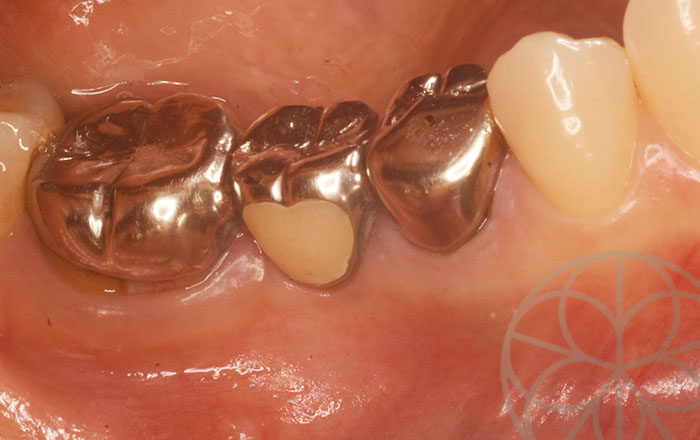

治療前状況①

左上3番目の歯は以前に歯科治療を受けておられましたが、根管治療が完了しておらず、根管治療剤が充填されていませんでした。カリエスの再発によって、歯が柔らかい状態に溶けていますが、柔らかい部分はカリエスディテクターという薬液でカリエスの部分を除去し、正常部分まで削りました。

残った残存部分の下方は、歯肉の位置よりも深く、骨がある部分まで達していたため、通常の方法では歯を保存することが難しいと判断しました。土台を立てて、エクスとルージョンという手法で、歯を引っ張り出して、健全部分が歯肉の上に来るように設定する必要があります。この処置を行わないと、この歯を助けることができず、残念ながら抜歯の適応になります。